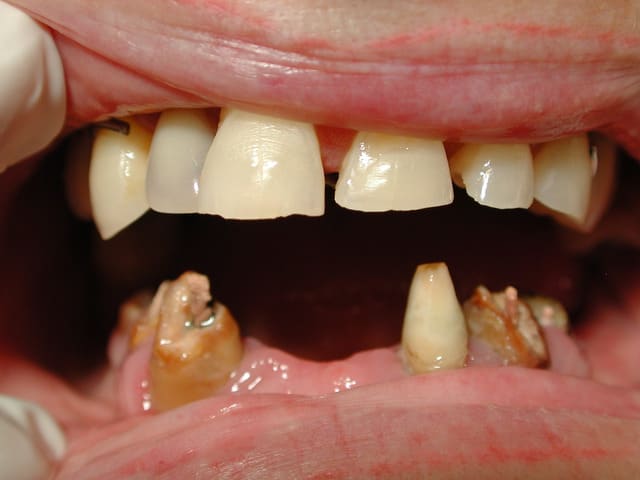

Voila un cas vite fait par un rentable: ramolli en 5 ans

Tu penses qu'on peut le rattraper en faisant inlay-core + bridge ?

Tu penses que j'ai perdu mon temps pour justifier des séances ?